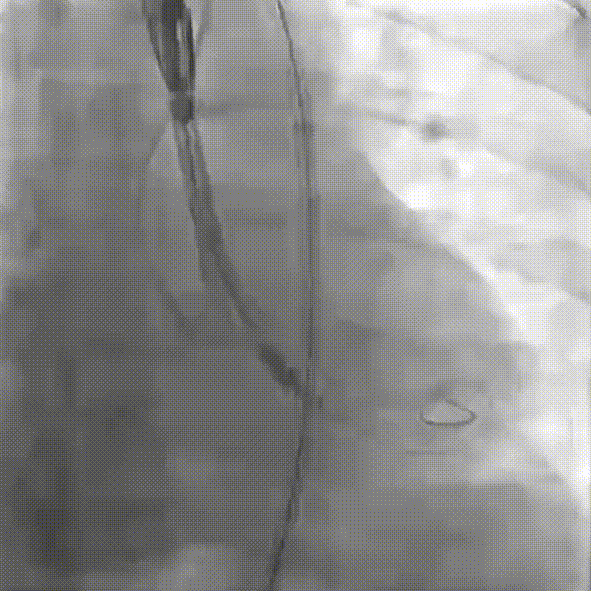

稳定脱钩

最终造影,位置形态良好

瓣膜位置固定良好无位移,瓣下2mm,平均跨瓣压差11mmHg,显著降低至,瓣周无反流;